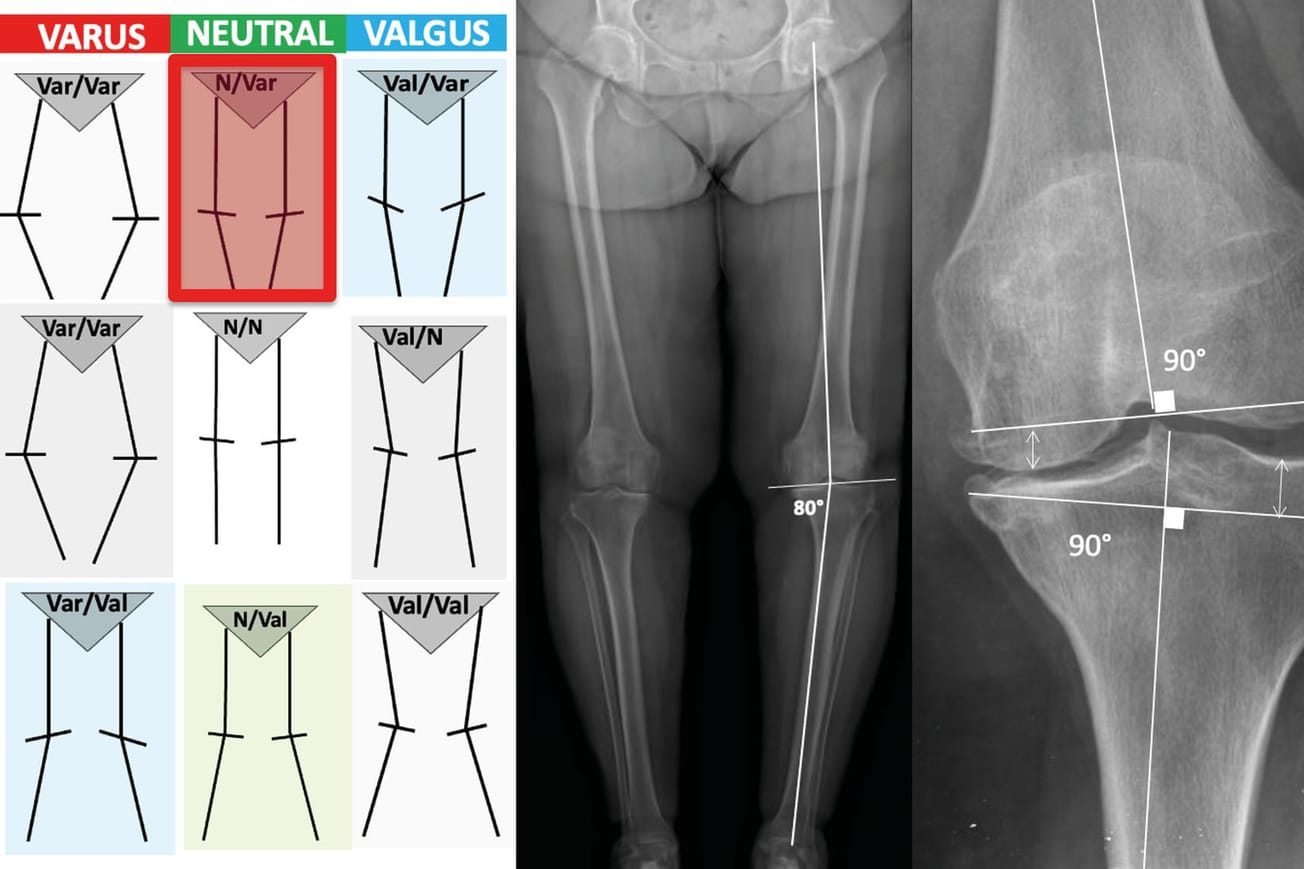

Mise au point L’alignement dans les Prothèses Totales du Genou , Matthew P. Abdel Mayo Clinic, Department of Orthopedic Surgery, 200 First Street S.W., Rochester, MN 55905, Etats-Unis , Tarik Aït Si Selmi Centre Orthopédique SANTY, 24, avenue Paul Santy, 69008 Lyon, France N°293 - Avril 2020 ● 19 min de lecture